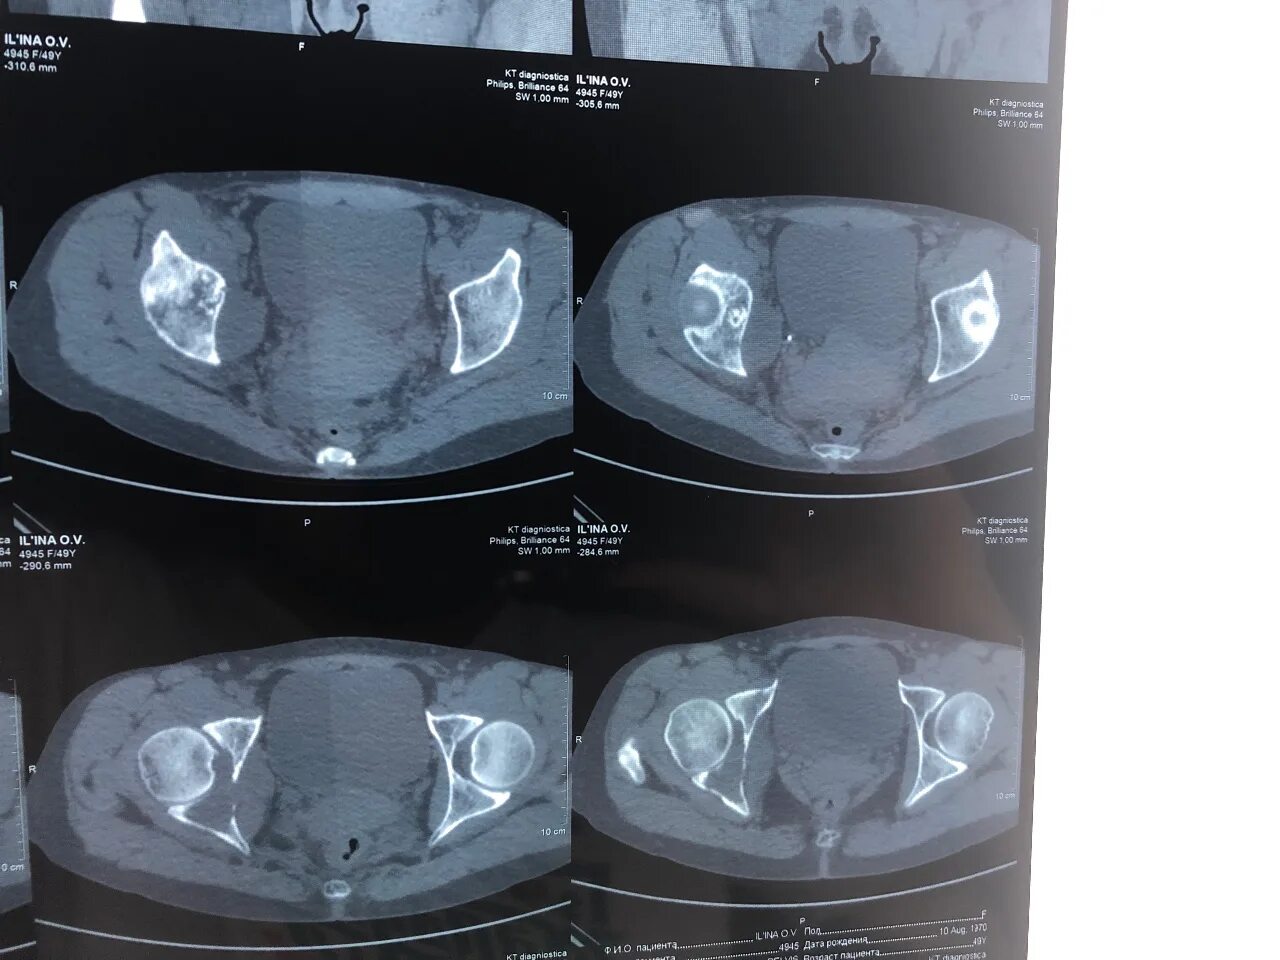

Можно делать кт через месяц